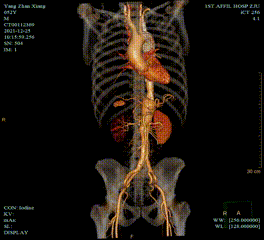

夹层近端封闭良好。夹层动脉瘤累及整个内脏区动脉,腹腔干、肠系膜上动脉假腔供血,腹腔干开口重度狭窄;右肾动脉真假腔供血,以假腔为主;左肾动脉真腔供血。肾下腹主动脉段无裂口,右侧髂外动脉存在裂口。

CT影像